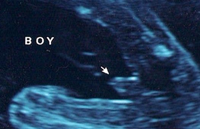

看著寶貝一切都很正常,我激動(dòng)的哭了,哈哈哈。。。。特別是上來的那張小雞雞的圖片,課清晰了,那個(gè)醫(yī)生都說好清晰啊,哈哈,醫(yī)生很厲害,她取的那個(gè)角度就是寶寶的屁股正下...

四維彩超怎么分辨男女?據(jù)稱,在彩超單上會(huì)印,頂頭最右邊有兩行字,是英文字母和數(shù)字組成的,第一行是日期,第二行是時(shí)間,如果第一行是M開頭,那就是male男,如果是F開頭就是...